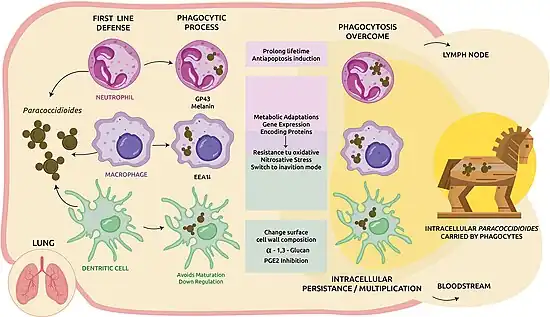

Mechanism

Primary infection, although poorly understood due to lack of data, is thought to occur through inhalation of the conidia through the respiratory tract, after inhaling fungal conidia produced by the mycelial form of P. brasiliensis.[14][21] This occurs predominantly in childhood and young adulthood, after exposure to agricultural activity.[13] Infection may occur through direct skin inoculation, although this is rare.[15]

After inhalation into the alveoli, there is rapid multiplication of the organism in the lung tissue, sometimes spreading via the venous and lymphatic systems.[14] Approximately 2% of people develop clinical features after the initial asymptomatic infection.[15]

The type of immune response determines the clinical manifestation of the infection, with children and HIV co-infected individuals most commonly developing the acute/subacute disseminated disease.[14] Most of those infected develop a Type 1 T-cell (Th1) mediated immune response, resulting in alveolitis and compact granuloma formation that control fungal replication, and latent or asymptomatic infection.[13][14] It then is thought to remain dormant in residual lung lesions and mediastinal lymph nodes.[21] A deficient Th1 cell response results in the severe forms of the disease. In these individuals, granulomas do not form, and the affected person develops Th2 and Th9 responses, resulting in activation of B lymphocytes, high levels of circulating antibodies, eosinophilia, and hypergammaglobulinemia.[13]

Lung involvement subsequently occurs after a dormant phase, manifesting in upper respiratory tract symptoms, and lung infiltrates on imaging.[15] The commonest, chronic form, is almost certainly a reactivation of the disease,[15] and may develop into progressive scarring of the lungs (pulmonary fibrosis).[23]

It can cause disease in those with normal immune function, although immunosuppression increases the aggressiveness of the fungus. It rarely causes disease in fertile-age women, probably due to a protective effect of estradiol.[24]

- ↑ Giusiano, Gustavo (2020). "The Trojan Horse Model in Paracoccidioides: A Fantastic Pathway to Survive Infecting Human Cells". Frontiers in Cellular and Infection Microbiology. 10: 605679. doi:10.3389/fcimb.2020.605679. ISSN 2235-2988.